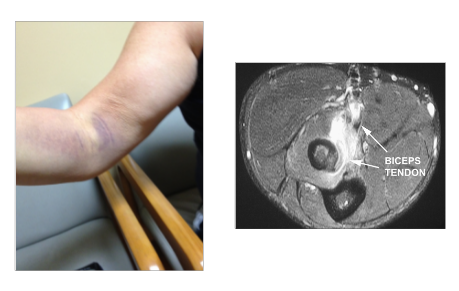

What is this?

Distal biceps tear

- Which part of the picture is the tendon and which is edema?

- 2- white is water, edema. balled up stuff is biceps tendon